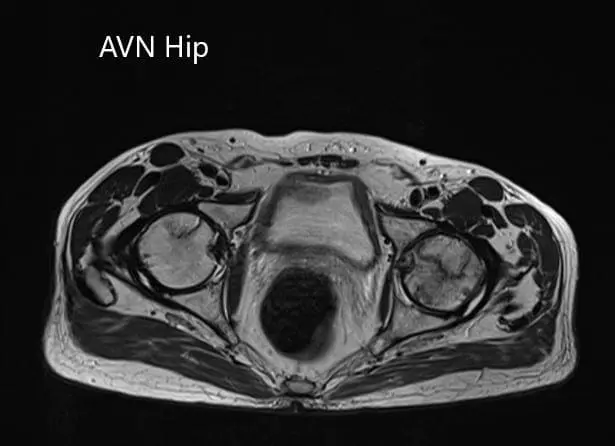

The left femoral head was collapsed with irregular contour and shows areas of altered signal intensity with a line of demarcation. Hypointense areas both on T1WI & T2WI seen in head suggestive of sclerosis. Surrounding marrow edema seen. A small amount of joint effusion with few osteophytes seen. The joint space was preserved.

The right femoral head shows areas of altered signal intensity with serpiginous demarcation line visualized, Hypointense areas both on T1WI & T2WI seen in head suggestive of sclerosis. The femoral head contour was normal. Surrounding marrow edema is seen. Small joint effusion is seen. Joint space is preserved.

Percentage necrotic areas in bilateral femoral heads are approximately 60-70 %.

Axial sections of the T1WI and T2WI of MRI.